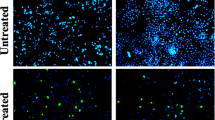

Migration assay

Migration assay is a hallmark assay to determine the effect of anticancer drugs against angiogenesis and metastasis. PA1 cells were created with wound and were treated with LD 50 value of the A. vasica extract. The cells were further observed for 0 h, 24 h, and 48 h against an untreated control. The observation implicated that the cells treated with the A. vasica extract did not show any growth in the clear area even after 48 h of incubation, whereas the untreated control was observed with almost complete growth in the clear area, which distinctly reveals that the A. vasica extract strongly inhibited the metastatic property in treated PA1 cells (Fig. 4).

The study of cell migration in cancer research is of particular interest as the main cause of death in cancer patients is related to metastatic progression. In order for cancer to spread and disseminate throughout the body, cancer cells must migrate and invade through the extracellular matrix (ECM), into blood circulation, and extravasate to form distant foci [31, 33]. In the current study, we used the cell culture wound closure to determine the antimetastatic properties of EAV. From our results, we observed that when compared with untreated control samples, the migration of PA1 cells is significantly decreased in EAV-treated groups which might indicate the antimetastatic properties of EAV [34, 35].